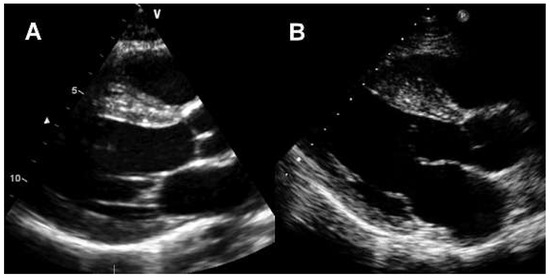

Since the first description of the athlete’s heart in 1899 by Henschen and Darling, the knowledge on cardiovascular adaptations to exercise conditioning h as expanded considerably. There is an ongoing debate about the true nature of the athlete’s hea...